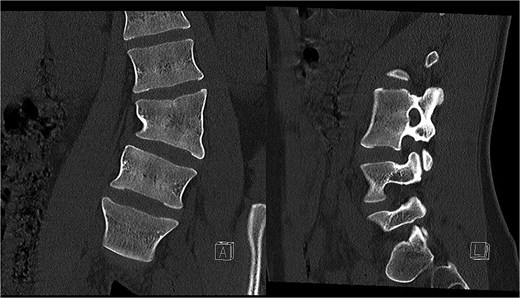

Preoperative CT demonstrating L3 hemivertebra; anteroposterior view (A) on the left side of the image, and lateral view (L) on the right side of the image.

CT-based 3D reconstruction revealed a semi-segmented hemivertebra at L3, resulting in a 32° Cobb angle of congenital scoliosis (Fig. 4). We decided to perform hemivertebra resection, L3 laminectomy, L2-L4 fixation with L3–4 cage fusion, and scoliosis correction. CT-based resection was 3D planned using EBS software (Fig. 6). Fixation from L2 to L4 was achieved using pedicle screws under fluoroscopic guidance, followed by L3 laminectomy. After accessing the L3–L4 disc space, a 3D real-time EMN-guided total resection of the L3 hemivertebra was performed (Fig. 6), and a cage with autogenous bone graft was inserted at the L3–L4 level. The left-sided L3 nerve was found to have an accessory branch, which was successfully preserved. Scoliosis was corrected using standard deformity correction maneuvers.